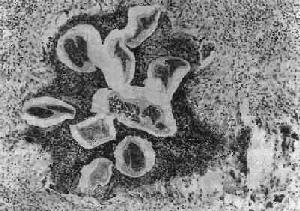

(1)淋巴管炎:多发生在较大的淋巴管,以下肢、精索、附睾、腹腔内淋巴管及乳腺等处较多见。肉眼观,急性期发炎的淋巴管呈一条红线样自上而下蔓延,形成所谓离心性淋巴管炎。当皮肤表浅微细淋巴管亦被波及时,局部皮肤则呈弥漫性红肿,称为丹毒性皮炎。镜下,常见淋巴管扩张、内皮细胞肿胀增生,管壁水肿增厚和嗜酸性粒细胞及单核细胞浸润。虫体死亡后对组织刺激强烈,引起凝固性坏死及大量嗜酸性粒细胞浸润,形成所谓嗜酸性脓肿。坏死组织中央可见死亡虫体断片及脱出在虫体外的微丝蚴,病变附近可找到Charcot-Leyden结晶。慢性期在脓肿周围出现类上皮细胞、巨噬细胞及异物巨细胞或Langhans巨细胞,形成结核样肉芽肿(图19-16)。随着虫体的钙化,肉芽肿逐渐纤维化,形成同心圆状排列的实心纤维索,使管腔完全闭塞,形成闭塞性淋巴管炎,而引起一系列继发改变。

丝虫性淋巴管炎

图19-16 丝虫性淋巴管炎

图中可见数个切断的死虫体,周围有嗜酸性脓肿及肉芽肿反应